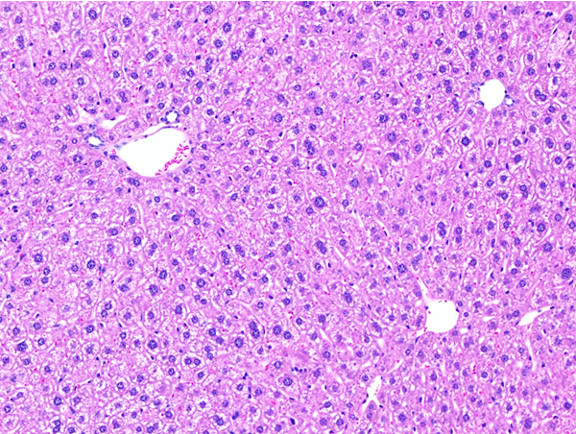

Figure 6: Histopathology for C57BL/6NTac mice placed on D09100310 diet (MASH B6NTac) or kept on chow diet (Control B6NTac) from 6 weeks of age. Animals were on diet for 27, 35 or 53 weeks. Hematoxylin and eosin (H&E) staining illustrates morphological changes including steatosis and infiltration of immune cells. Activated HSCs were identified in liver sections by using a rabbit polyclonal antibody to alpha-smooth muscle actin (a-SMA) (1:500 dilution; ab5694; Abcam, Cambridge, MA) which was detected by an anti-rabbit IgG embedded polymer with embedded horseradish peroxidase and visualized with 3,3′-diaminobenzidine (DAB) chromogen (Agilent, Carpentaria, CA). Hepatocellular lipid droplets were identified by visualization of the lipid-binding protein adipophilin known to be expressed in steatotic livers. Sections of livers were probed using a rabbit polyclonal anti-adipophilin antibody (1:200 dilution; NB110-40877, Novus Biologics, Littleton, CO) which was detected by an anti-rabbit IgG embedded polymer with embedded horseradish peroxidase and visualized with 3,3′-diaminobenzidine (DAB) chromogen (Aligent, Carpentaria, CA). Picrosirius red (PSR) staining illustrates collagen I and III fibers and is used to measure fibrosis. The same individual MASH or control animal is shown for all four stains in a particular time point. Different individual animals were used for each time point (i.e. data is not longitudinal by animal). Histopathology services provided by IDEXX BioAnalytics.

General chow control mouse findings: All mice were bright, alert and responsive. Fur coat appeared well groomed with mild oily appearance. Intermittent lighter colored tips on hairshafts of fur coat. Body condition score was 3-4 for controls at 33 and 41 weeks of age and 4 for controls at 59 weeks of age. All animals had adequate to plentiful mesentary and subcutaneous adipose tissue present. Liver appeared grossly dark pink with uniform color and texture, except in 2 males at 59 weeks for which liver appeared mildly pale with a mild icteric tinge in 2 of 5 males. No masses or lesions were observed on serosal or cut side of livers.